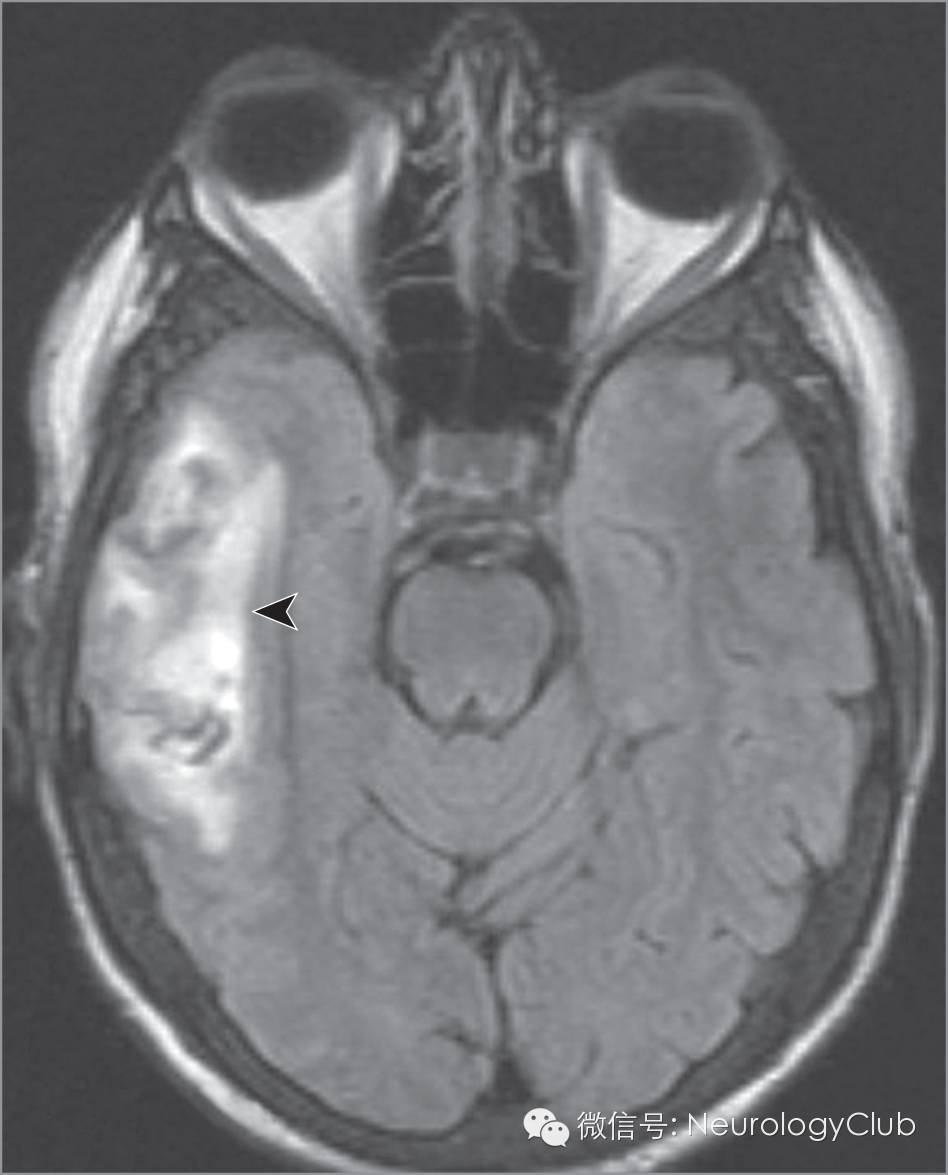

30岁男性,右侧颞叶病灶

30岁男性,因2次强直-阵挛发作来到急诊室,该症状出现前的一周内曾有数次头痛。既往罹患镰状细胞病。神经系统查体未见明显局灶性体征。实验室检查结果如下:血红蛋白,11.2 g/dL;平均红细胞容积,95.2μm^3;血小板,736 ×10^3/μL;电泳提示血红蛋白S水平52%。患者诉每年约有1次镰状细胞危象,并因缺血性坏死行左髋关节置换术。头颅MRI提示右侧颞叶较大面积出血性梗死(图1),提示Labbe静脉血栓形成,磁共振静脉成像证实了这一推断(图2)。患者接受静脉切开术(放血200ml)与静脉补液治疗,目标是把血红蛋白水平降至10g/dL以下。血栓形成倾向检查提示VIII因子水平升高

(图1:黑水像提示右侧颞叶较大面积出血性梗死)